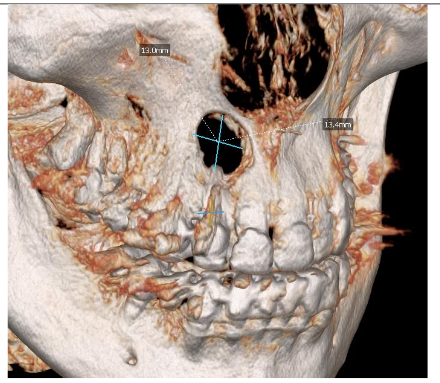

3D scan confirmed that cyst in the right maxilla totally damaged both laminas

Radiographic examination revealed necrosis around the apex of tooth 12, with CBCT scans showing damage to both the buccal and palatal cortical plates. A decision was made for one-step treatment, and anticoagulant therapy was not interrupted.